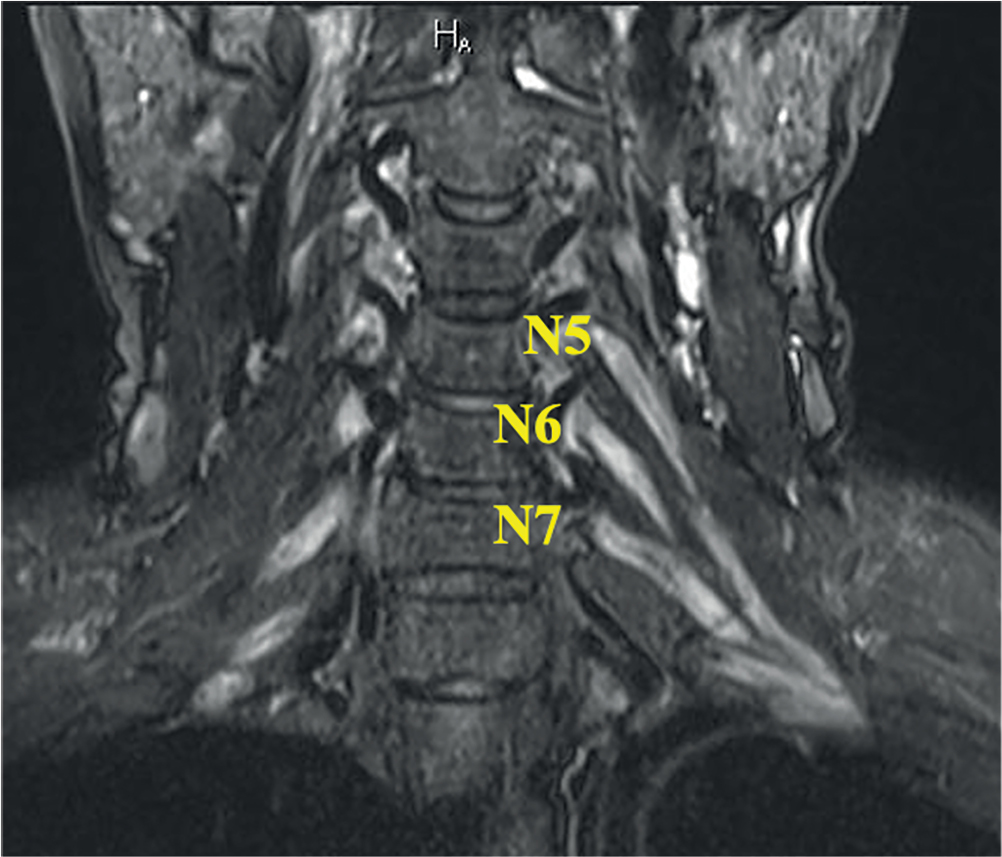

Рис. 5. МРТ ПС пациента с ММН (катамнез 10 лет, исследование выполнено до начала патогенетической терапии). В режиме STIR в коронарной проекции отмечается локальное утолщение N7 слева на уровне первичного ствола до 11 мм, сопровождающиеся повышением МР-сигнала. Толщина других элементов ПС не изменена, однако МР-сигнал от них повышен с двух сторон.

Fig. 5. BP MRI in a MMN patient (10-year follow-up history, pre-therapy assessment). The coronal STIR MRI showed left-sided local N7 (≤ 11 mm) primary trunk thickening, with hyperintense signal. Thickness of other BP elements remained unchanged; however, hyperintense MRI signal was registered bilaterally.